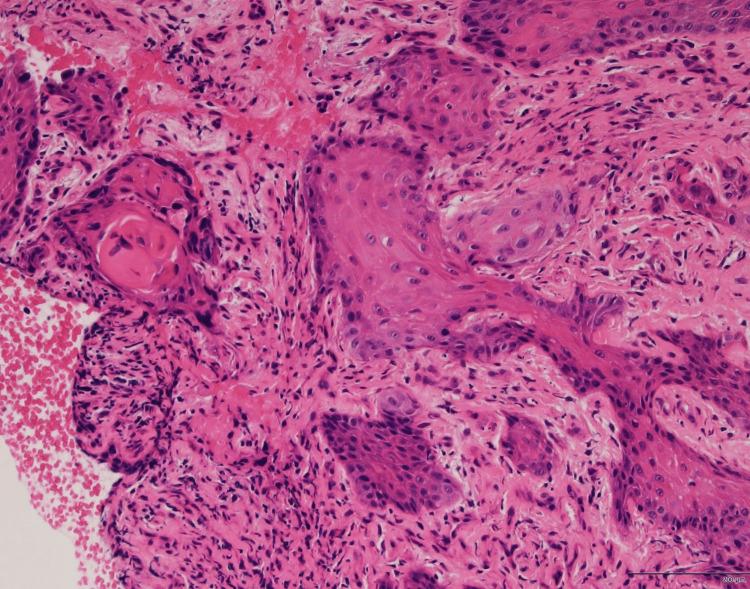

组织学分析证实了分化良好的鳞状细胞癌(SCC)(图2),根据改良的匹兹堡分类,该癌被归类为T4,没有颈部淋巴结受累或远处转移。正电子发射断层扫描计算机断层扫描(PET-CT)也没有显示颈部淋巴结或远处转移的证据。

图2 标本苏木精和伊红染色显示非典型鳞状上皮侵入基质,证实了分化良好的鳞状细胞癌的诊断